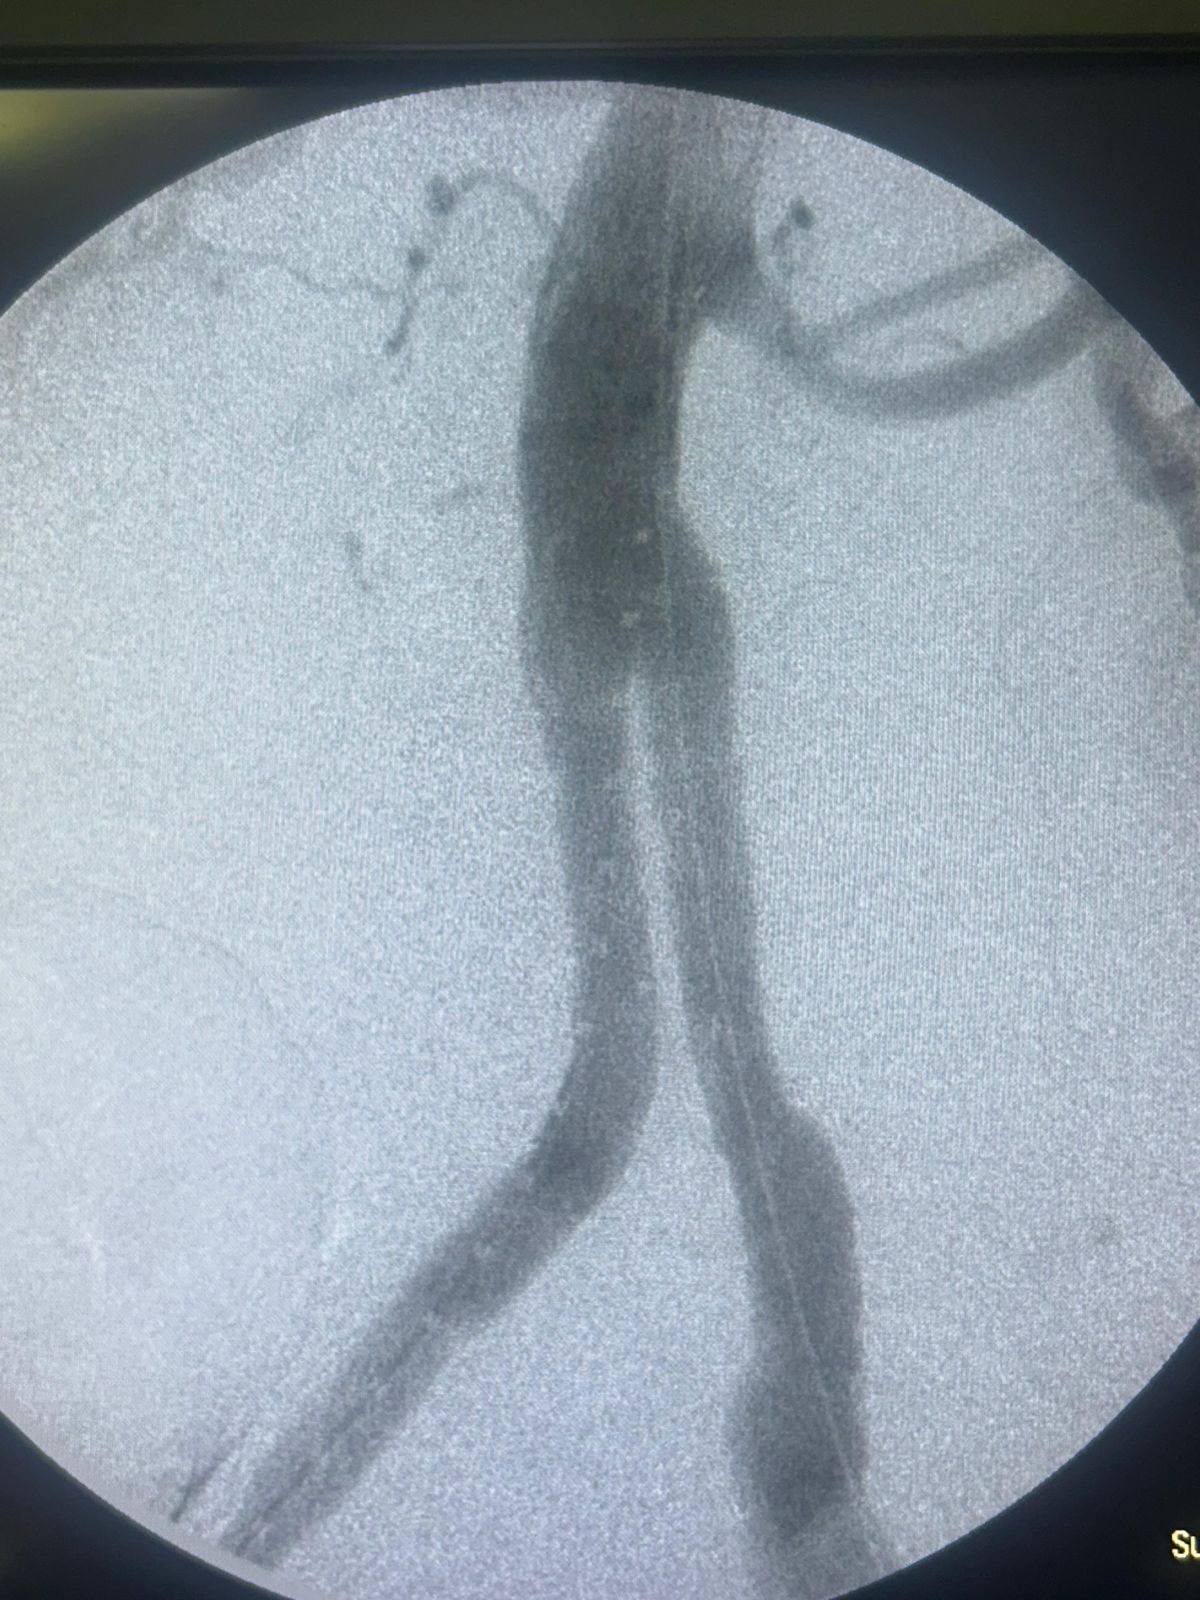

En Ecuador se realizó con éxito el primer procedimiento endovascular para el tratamiento combinado de Aneurisma de Aorta Abdominal (AAA) e ilíaco, utilizando la endoprótesis Minos™ Ultra Low Profile de MicroPort Endovastec, una solución avanzada diseñada para accesos vasculares complejos y anatomías desafiantes.

👨⚕ El paciente, un hombre de 66 años, presentaba un AAA de 74 mm y un aneurisma de Ilíaca Primitiva de 70 mm, con accesos finos y tortuosos y un cuello distal de aorta de 23 mm.

El abordaje incluyó:

Embolización de Hipogástrica derecha con coils

Implante de endoprótesis aorto-bi-ilíaca hasta la ilíaca externa derecha e ilíaca primitiva izquierda